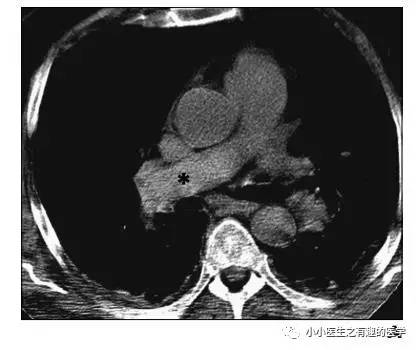

下面是另外一个:

星号的地方。

再来一个

很明显:扯蛋肺栓塞。